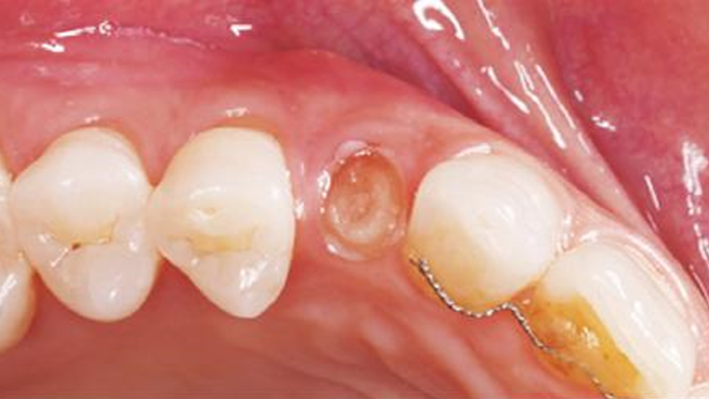

Clinical case: Patient-centered approach: treatment strategy for Root Membrane Technique & delayed implant placement

- Courtesy of Dr. Yoshiharu Hayashi, Japan -

Socket Shield Technique, anterior esthetics, maxillary anterior, esthetic, esthetics, delayed implant placement, socket preservation, AnyRidge, Root Membrane Kit, Root Membrane Technique, Partial Extraction Therapy, PET, esthetic zone, fuse abutment, Dr. Yoshiharu Hayashi,#11,#21,#22

AnyRidge implant system, fuse abutment Root membrane kit, PET Kit

“Advanced IntermezzoTM – one-piece solution for immediate placement & esthetic result in anterior region or narrow space.”